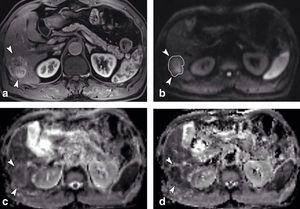

Intravoxel incoherent motion (IVIM) imaging is a concept and a method initially introduced and developed by Le Bihan et al. to quantitatively assess all the microscopic translational motions that could contribute to the signal acquired with diffusion MRI. In biological tissues, these motions essentially are molecular diffusion of water and microcirculation of blood in the capillary network (perfusion). The concept introduced by D. Le Bihan is that water flowing in randomly oriented capillaries (at the voxel level) mimics a random walk ("pseudo-diffusion"). According to IVIM theory, the fast component of diffusion (represented by D*) is related to microperfusion (mainly on low b values, 0-100 s/mm2), whereas the slow component (represented by D) is linked to pure molecular diffusion. Owing to this bi-compartmental model, the signal decay of IVIM DWI was described using a bi-exponential model. Using IVIM-based analysis, it is possible to derive quantitative indexes that describe conventional ADC (ADCtotal), tissue water diffusivity (pure diffusion/ D), tissue perfusion (pseudodiffusion coefficient/ D*), and the perfusion fraction of tissues (f), which can also be displayed as parametric maps. Because there are four fitted parameters, a minimum of four b values are needed to characterize bi-exponential signal attenuation, though this choice is not recommended. A larger number of b values would provide more data support for the estimates and would enable parameter uncertainties to be evaluated, which is not possible with four b values. IVIM model can be used on clinical applications in the liver, pancreas, prostate and other well-perfused body organs. Figure shows a 3.2 cm surgically confirmed HCC in 59-year-old man. The mass (arrowheads) showed heterogeneous enhancement during arterial phase (a) and high signal intensity on DWI (b factor, 800 sec/mm2) (b). The tumor showed a slightly lower ADC value (arrowheads) than surrounding liver parenchyma on ADC map (c). True D was obviously lower (arrowheads) than liver parenchyma on D map (d) (Yoon et al. 2013.